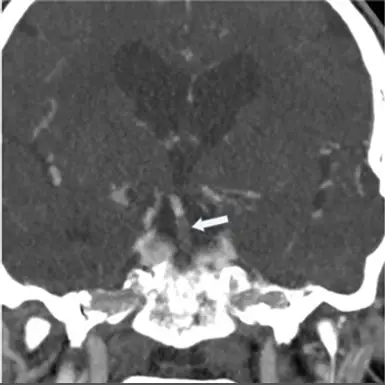

60歲男性,臨床表現為言語困難和步態不穩。下圖CTA影像中箭頭所指為何種狀況?

- 影像掃描技術:此為一張腦部電腦斷層血管攝影 (CT Angiography, CTA) 的冠狀面重組 (Coronal view) 影像。

- 在腦幹 (特別是橋腦 Pons) 的前方(即橋腦前池 Prepontine cistern),可以觀察到一條沿著正中線垂直向上行走的單一粗大血管,此即為「基底動脈 (Basilar artery)」。

- 白色箭頭所指處:清楚顯示基底動脈管腔內出現了顯著的對比劑充盈缺損 (filling defect) 與血管截斷 (abrupt cutoff) 現象。正常且血流暢通的血管在 CTA 上應呈現連續的亮白高密度影像,然而箭頭處呈現一段低密度暗區,代表該段血管被血栓 (thrombus) 或栓子 (embolus) 所填塞,阻斷了血流。

- 綜合上述,此影像呈現了極為典型的「基底動脈栓塞」。

- 影像解剖驗證:在 CTA 的冠狀切面中,白色箭頭所指的血管位於顱底正中央、腦幹前方,這正是基底動脈 (Basilar artery) 的專屬解剖位置。箭頭處明確標示出血管腔內的充盈缺損 (filling defect),證實了血栓阻塞的存在。 結合上述兩點,無庸置疑地可以確立診斷為基底動脈栓塞 (Basilar Artery Occlusion),因此最正確的答案為 D。